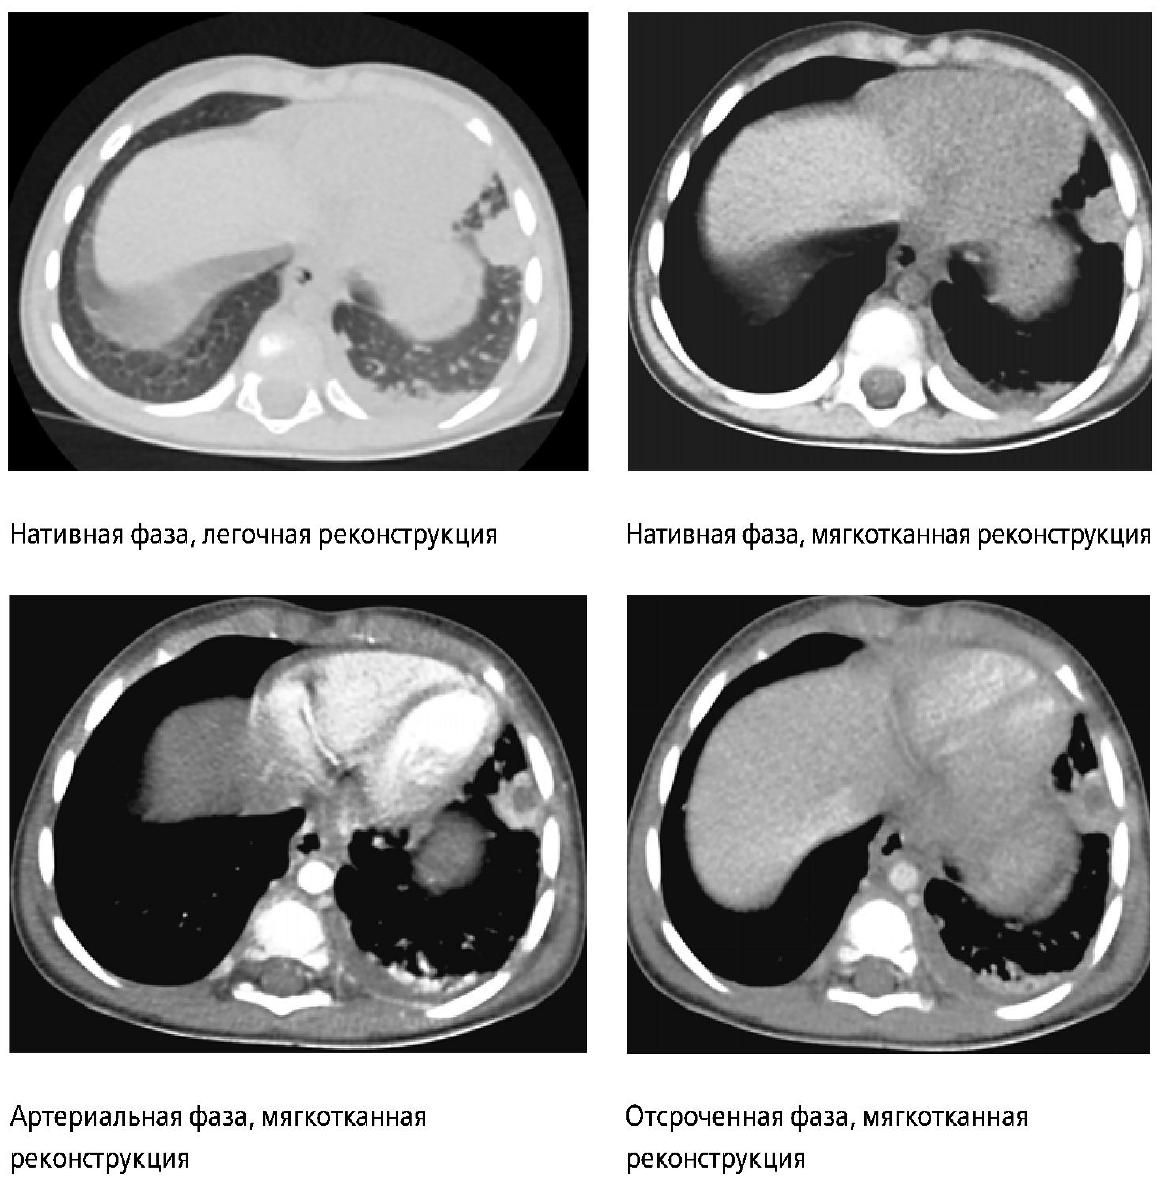

На основании результатов УЗИ были проведены компьютерная томография и рентгенография органов грудной клетки, бронхоскопия.

R-грамма выполнена в стандартной укладке.

Мягкие ткани и костные структуры без видимой патологии.

- Справа определяется затенение легочного поля за счет инфильтрации, с наличием овальных просветлений в латеральных отделах, с достаточно четкими контурами, толстой стенкой (воздушные полостные образования - полости деструкции).

- Легочный рисунок обогащен за счет сосудистого компонента, сгущен (больше справа). Корень правого легкого малоструктурный, корень правого легкого проекционно перекрыт тенью средостения. Уплотнена, утолщена паракостальная плевра справа, с затенением реберно-диафрагмального синуса (наличие жидкости в плевральной полости справа).

- Тень средостения с четким, ровным контуром.

- Купол диафрагмы слева имеет четкие контуры, расположен на обычном месте, справа купол диафрагмы не дифференцируется в латеральных отделах.

- В подключичной области справа определяется тень центрального венозного катетера, дистальный конец которого - на уровне верхнего края тела позвонка Th6.

Рис. 5. Рентгенограмма грудной клетки в прямой проекции

Рис. 5 (а, б).Компьютерные томограммы органов грудной клетки мальчика М. на десятый день болезни в аксиальной и фронтальной плоскостях с контрастным усилением.

Заключение: Рентгенологическая картина правосторонней полисегментарной деструктивной пневмонии. Рентгенологические признаки жидкости в правой плевральной полости.

КОМПЬЮТЕРНАЯ ТОМОГРАФИЯ

На полученных томограммах толщиной среза 1 мм и мультипланарных реконструкциях, до и после введения контраста «Омнипак 350».

- Легкие: правое легкое субтотально коллабировано (за исключением части верхней доли), смещено медиально вниз. Левое легкое воздушное, несколько уменьшено в размерах, смещено лате-рально, без массивных зон инфильтрации.

- Сохранен просвет правого главного, правых долевых бронхов. Сегментарные бронхи прослеживаются фрагментарно в средней и нижней долях, в верхней видны.

- Слева просветы бронхов прослеживаются до сегментарных.

- Угол бифуркации трахеи меньше 90 градусов.

- Жидкость в плевральных полостях справа во всех отделах, по всем поверхностям до 34 мм, слева не определяется. Контуры диафрагмы четкие.

- После контрастного усиления определяется снижение накопления контрастного вещества средней и нижней долями правого легкого. В верхней и средней долях вероятно наличие сообщающихся полостей неправильной формы, размерами до 15 х 11 мм, некоторые из которых сообщаются с бронхами.

Заключение: КТ-картина правосторонней деструктивной пневмонии, с массивными зонами ишемии, множественными полостями и коллаби-рования легкого, вызванного массивным плевральным выпотом справа (рис. 5).